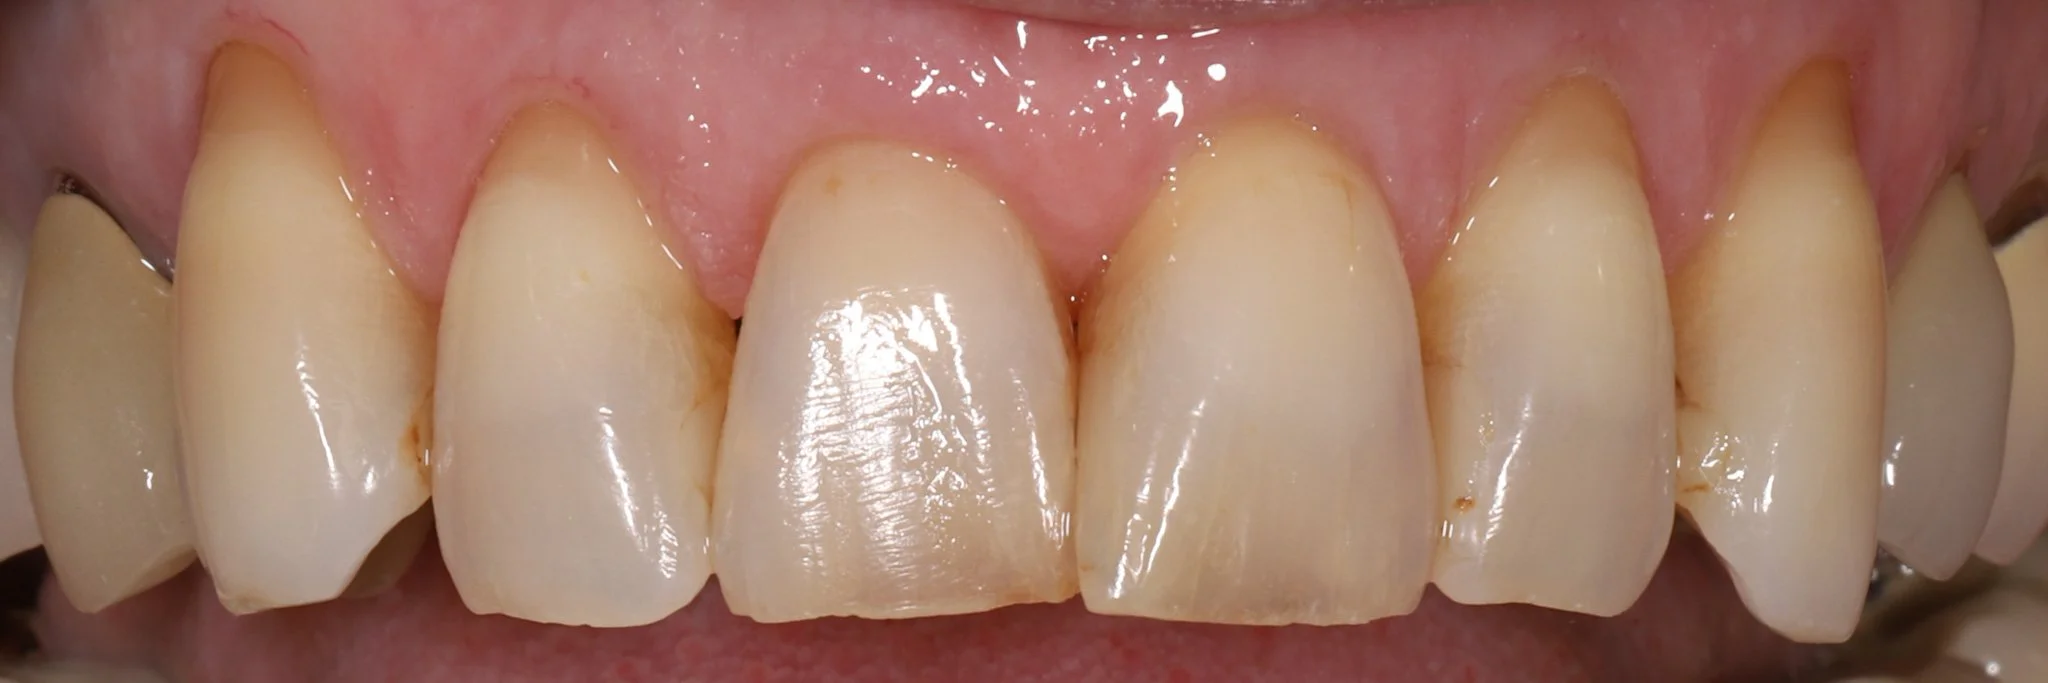

Close-up image of upper front teeth showing mismatched crowns, chipped and worn teeth with acid erosion.

Before: Heavy acid erosion, wear, poor aesthetics

Close-up of a person's upper front teeth, showing straight, white teeth with healthy gums with ideal aesthetics.  These teeth were restored with porcelain crowns.

After: Protected teeth with proper aesthetics and function